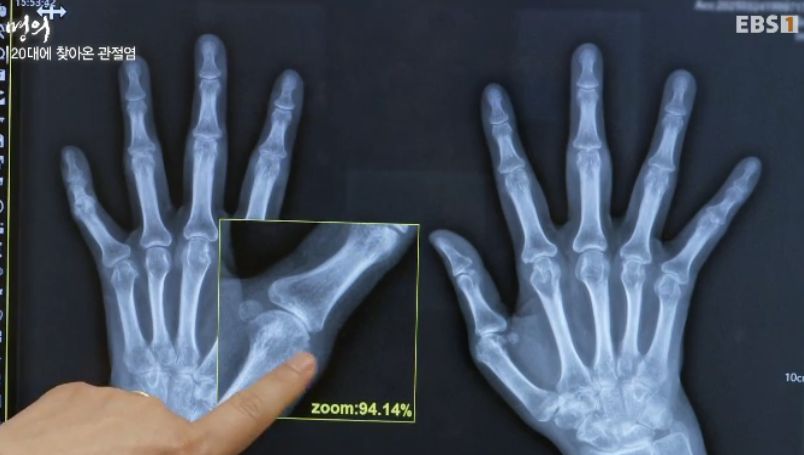

20대에 찾아본 관절염

"류마티스는 염증이 연골을 녹이기 때문에

땅에 가라앉듯이 두 개가 붙어버려요"

29살에 관절변형된 사례)

진단은 피검사와 엑스레이. 필요하면 관절초음파 등.